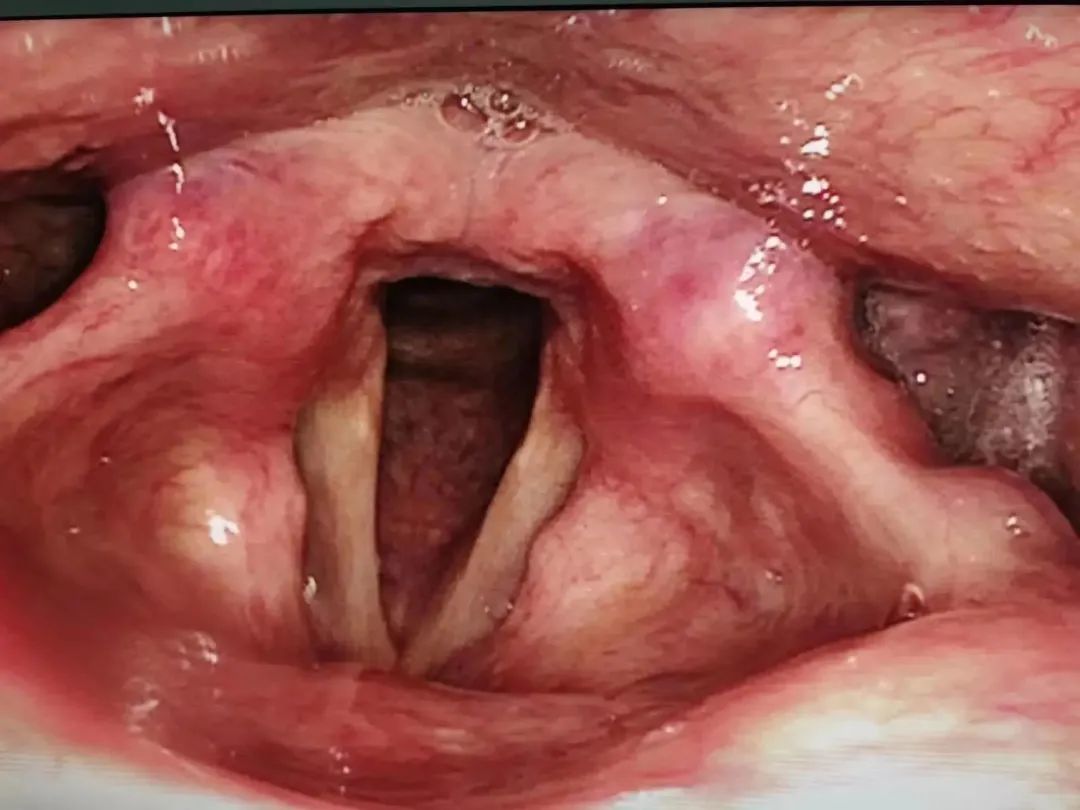

术前

术后1个月

术后6个月

术后申先生恢复情况良好,术后6个月复查喉镜,结果显示双侧声带光滑,发音有力,已恢复正常生活。该技术在邯郸地区为创新开展。